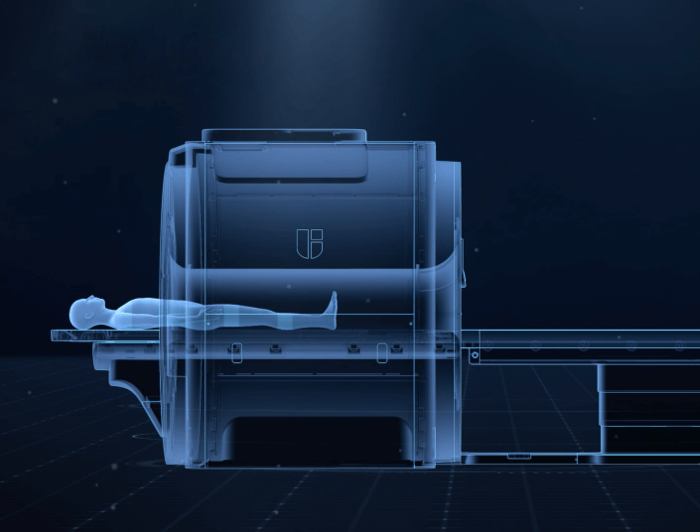

智云磁体

自主研发的匀场技术,优异的磁场均匀度。

智云梯度

智能涡流补偿技术,高梯度性能。